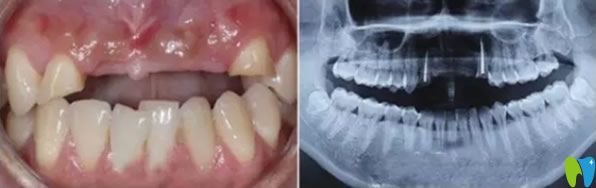

一次意外導(dǎo)致老公門(mén)牙缺失,在一家小診所做的烤瓷牙,這幾年用著還可以,但是前幾天發(fā)現(xiàn)牙齦萎縮很?chē)?yán)重 ,明顯一個(gè)坑。三十出頭小伙子看著像四十多歲大叔,這可怎么辦?網(wǎng)上說(shuō)牙齒缺失可以通過(guò)種植牙來(lái)修復(fù),我們也不知道有沒(méi)有年齡限制,老公都30多歲了還能做種植牙?成都瑞爾口腔在我們這的口碑挺不錯(cuò)的,我就陪老公來(lái)咨詢(xún)。

來(lái)院后面診的是郝亦工醫(yī)生,詳細(xì)檢查后,說(shuō)老公的門(mén)牙可以通過(guò)牙齒種植來(lái)修復(fù),同時(shí)也能改善牙齦萎縮的現(xiàn)狀。郝主任說(shuō)種植牙沒(méi)有年齡限制,只要身體無(wú)疾病,都可以種植。

郝醫(yī)生通過(guò)醫(yī)學(xué)種植技術(shù),根據(jù)老公牙齒狀況設(shè)計(jì)種植方案。他將種植體與人體兼容性高的鈦金屬精準(zhǔn)植入缺牙區(qū)的牙槽骨內(nèi),等三個(gè)月后,人工牙和牙槽骨緊密結(jié)合,再做烤瓷牙、全瓷牙冠。郝醫(yī)生植入牙根手術(shù)完成后,老公從手術(shù)室出來(lái)牙齦看著就沒(méi)有之前那么憋了,飽滿(mǎn)了許多。